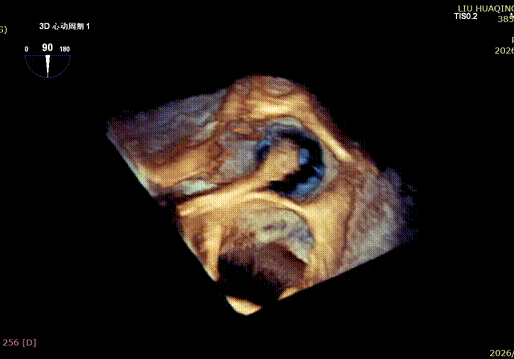

The operation was performed in a hybrid operating room and completed under the guidance of real-time three-dimensional transesophageal echocardiography (3D TEE) and X-ray fluoroscopy throughout the entire process.

Mitral Valve Repair Stage: Via the transfemoral venous approach, a 4.0 cm atrial septal puncture was performed, and one mitral valve clip was selected. The unique feature of wide-angle deployment effectively resolved the issue of excessive leaflet tension during valve clip closure. Under the precise guidance of ultrasound, one clip was successfully implanted at the site of the widest regurgitation in the A2-P2 segment of the mitral valve. Immediate postoperative TEE assessment showed that mitral regurgitation was reduced to trivial (1+), the mean transvalvular pressure gradient was only 3 mmHg, and pulmonary venous retrograde flow was significantly improved.

Tricuspid Valve Annuloplasty Stage:Subsequently, via the right internal jugular vein approach, the K-clip® transcatheter tricuspid valve annuloplasty system was delivered to the right atrium. With the assistance of three-dimensional ultrasound stereoscopic views, a 12T clip was successfully implanted at the posteroseptal commissural annulus of the tricuspid valve, and a 14T clip at the anteroposterior commissural annulus, achieving effective constriction of the dilated annulus. Immediate postoperative assessment demonstrated that tricuspid regurgitation was improved from severe (4+) to mild (1+) instantaneously.

1.Intraoperative baseline assessment of regurgitation severity

2.Placement of large sheath and delivery system under ultrasound guidance

3.Steer and rotate the delivery system to target the lesion, and implant the anchor screw via the 3D MPR plane

4.Land the clamping arms after orientation adjustment, and close the clamping arms slowly

5.Perform the same procedure for the second clip; the clip morphology is stable under 3D imaging